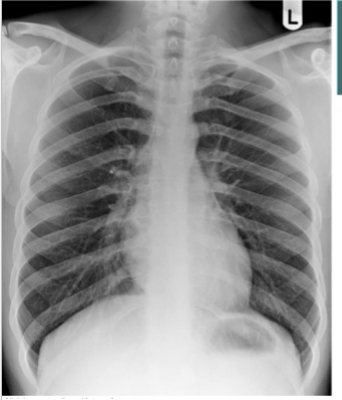

PA CXR

What is this

AP